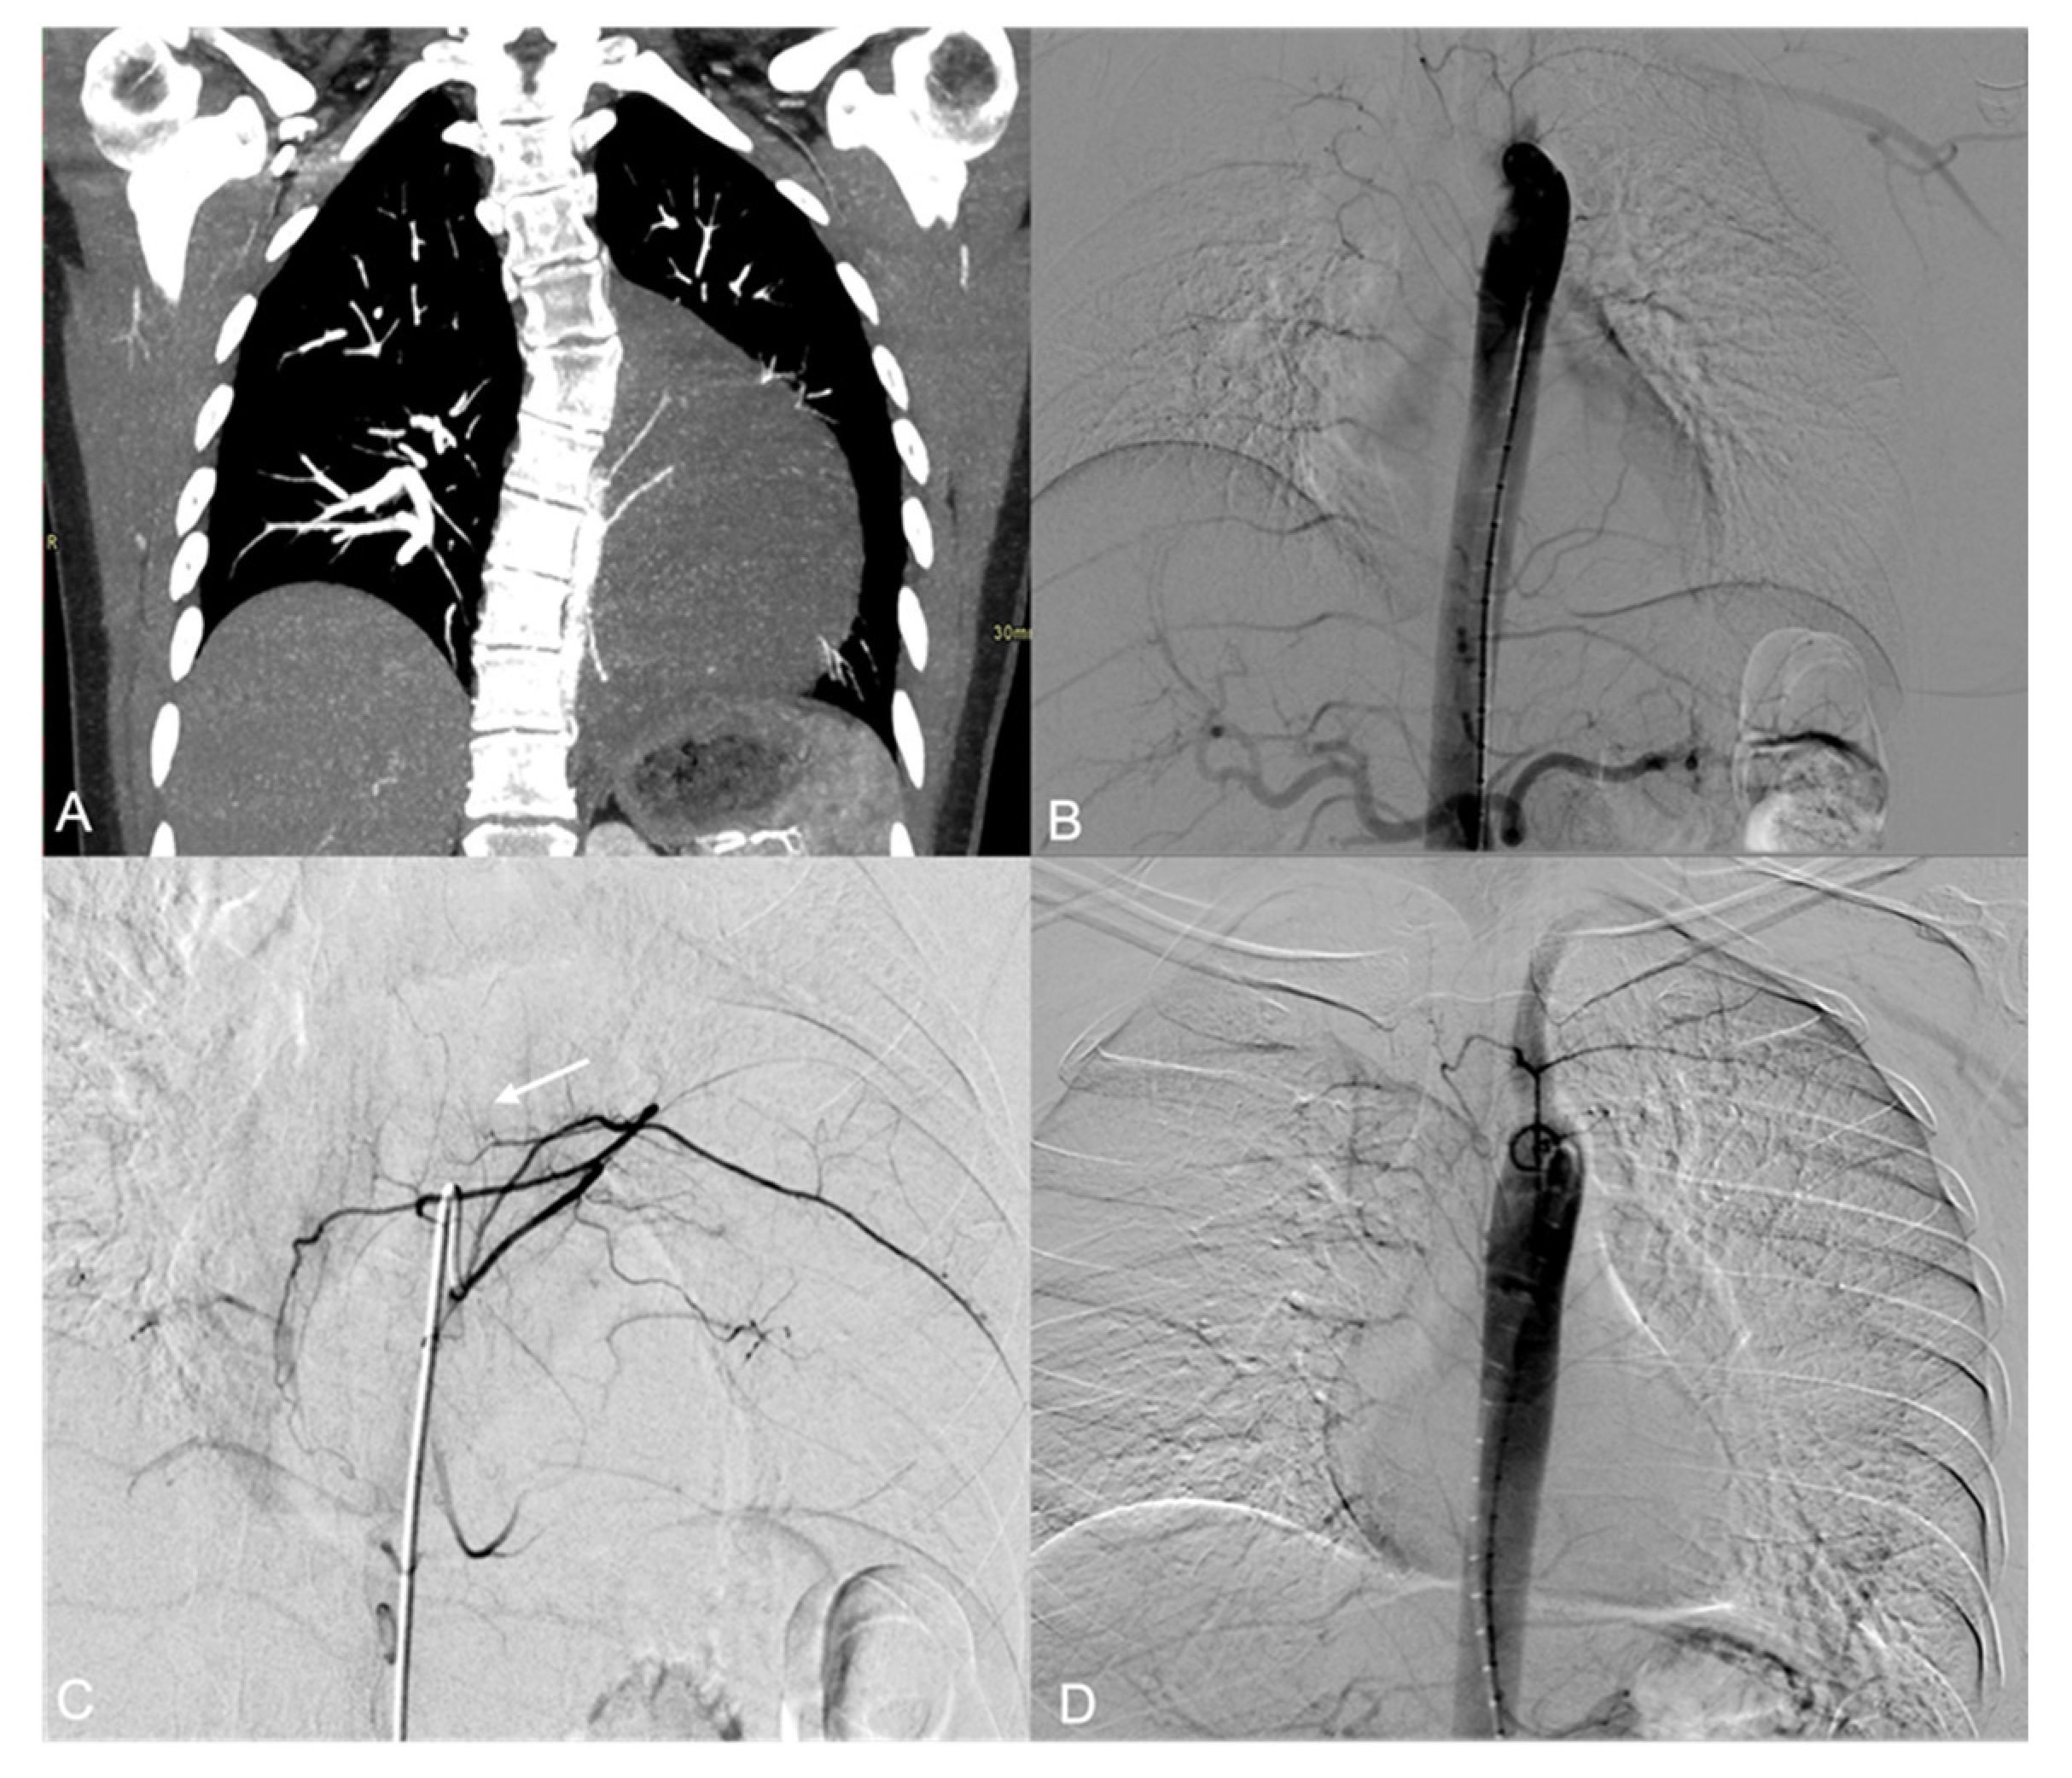

3. Results